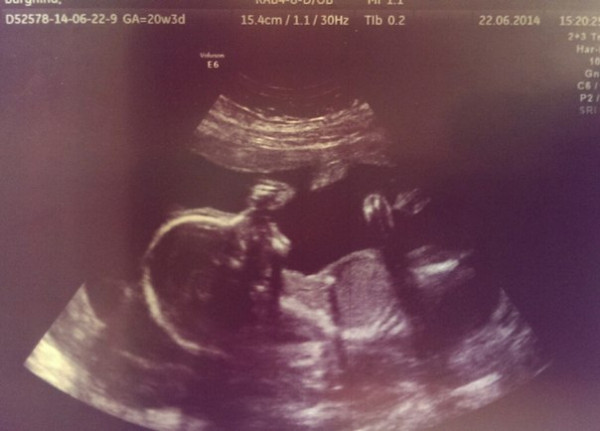

21 неделя беременности мальчиком

21 неделя беременности мальчиком 115 фотографий